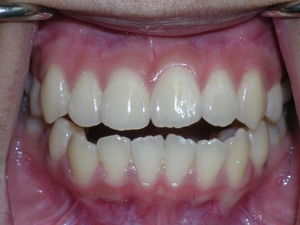

So here’s a case of an open bite, with a protrusion. There was a fair degree of crowding as well.

Here are the results.